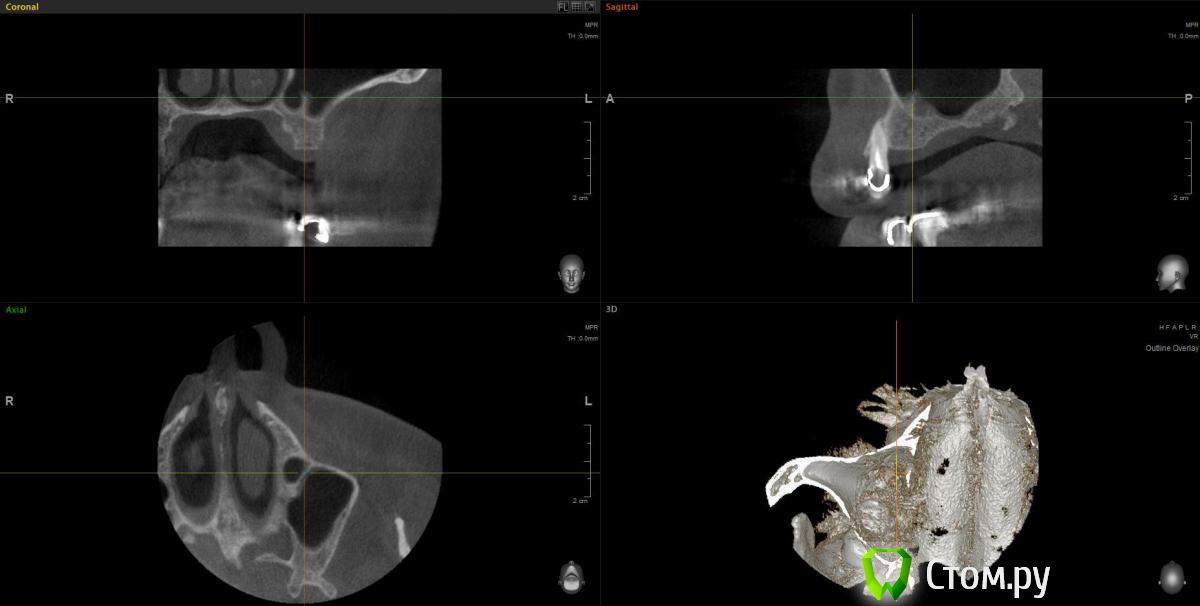

wladdX Опубликовано 11 февраля, 2014 Поделиться Опубликовано 11 февраля, 2014 (изменено) Прошу прощения за вторжение в чужую тему (администратор, поправьте), но ситуация похожа. Т.е. помимо синус-лифтинга надо увеличить ширину альвеолярного отростка. Предполагаю поступить примерно, как продемонстрировал Mane выше. Но может подойдёт "метод полужёстких каркасов? Кстати септа в пазухе замысловатая. По поводу остальных сегментов и прочих проблем - пациент на них не настроен, интересует его только зона 25,26,27 Изменено 11 февраля, 2014 пользователем wladdX Ссылка на комментарий

Sahan Опубликовано 11 февраля, 2014 Поделиться Опубликовано 11 февраля, 2014 Ну для планирования такой работы при КТ во рту должен был быть хирургический шаблон. А так никаких проблем. Открытый синус , плюс имплантаты , плюс сетка. Ссылка на комментарий